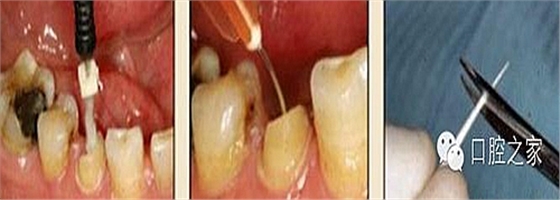

使用全酸蝕粘結(jié)系統(tǒng)粘接纖維樁時,需要應(yīng)用磷酸凝膠對根管進行酸蝕處理,然后再徹底沖洗干凈。根管內(nèi)酸蝕劑的殘留是臨床上經(jīng)常發(fā)生且容易被忽視的問題,也是影響纖維樁粘接的重要因素之一。單獨使用三用槍即使反復(fù)沖洗也很難將根管內(nèi)的酸蝕劑清除干凈,尤其是后牙根管。臨床建議應(yīng)用注射器、三用槍和柱狀毛刷,三者聯(lián)合使用反復(fù)沖洗,以免酸蝕劑殘留于根管內(nèi)(圖 19-1至圖 19-4)。有條件者也可使用超聲波蕩洗根管。

圖19-1:冠部及根管全酸蝕。圖19-2:三用槍沖洗。圖19-3:注射器沖洗。 圖19-4:根管毛刷清洗。